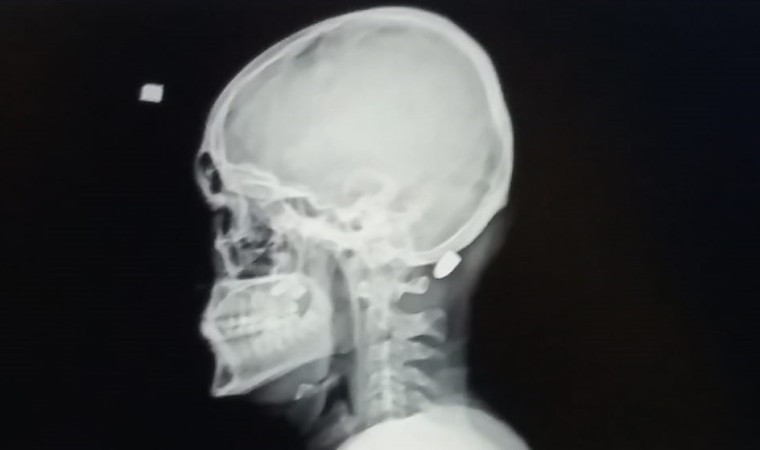

Kentte yetkililerin tüm uyarılarına rağmen yorgun mermi vakalarının arkası kesilmiyor. Yorgun mermi vakalarında kimileri hayatını kaybediyor, kimileri yaralanıyor, kimileri de sakat kalma tehlikesi ile karşı karşıya kalıyor. Trabzon’un Ortahisar ilçesinde 9 Nisan 2016 tarihinde Mustafa Mandıralı (22) isimli inşaat işçisi işe giderken otobüs durağı yakınında nereden ve kim tarafından atıldığı belli olmayan ve "Yorgun mermi" diye tabir edilen merminin hedefi oldu. Merminin başına isabet etmesi sonucu Mandıralı ağır yaralandı.